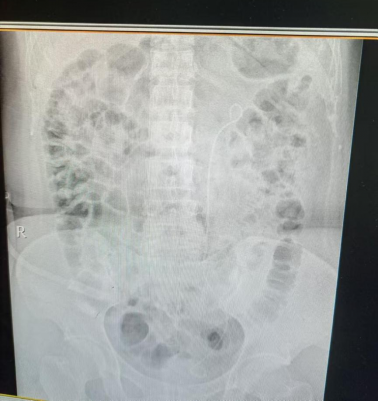

近日,家住九江经开区的柯姓女士,左侧腰部突发疼痛不适,因疼痛剧烈,为就近治疗原则急至我院外科就诊,经腹部超声检查后诊断为:左侧肾积水及输尿管结石,完善泌尿系CT检查后确定结石位于左侧输尿管上段,且结石体积为12mm*5mm,左肾积水较重,因结石体积较大,如果行传统体外冲击波碎石,碎石后可能出现排石效果差,肾积水难以缓解等情况,经与患者及家属沟通后,建议患者行钬激光碎石手术,一开始患者表示犹豫不决,经过反复向患者阐述,患者了解到:我院输尿管软镜为新进口设备,手术视野清晰,设备条件完好;我院泌尿外科有九江市第一人民医院总院泌尿外科专家长期驻扎我院,手术经验相当丰富。患者及家属深入了解后欣然接受在我院行手术治疗。经过术前系列检查后很快为柯女士安排了手术,术后恢复良好,近日已顺利出院。